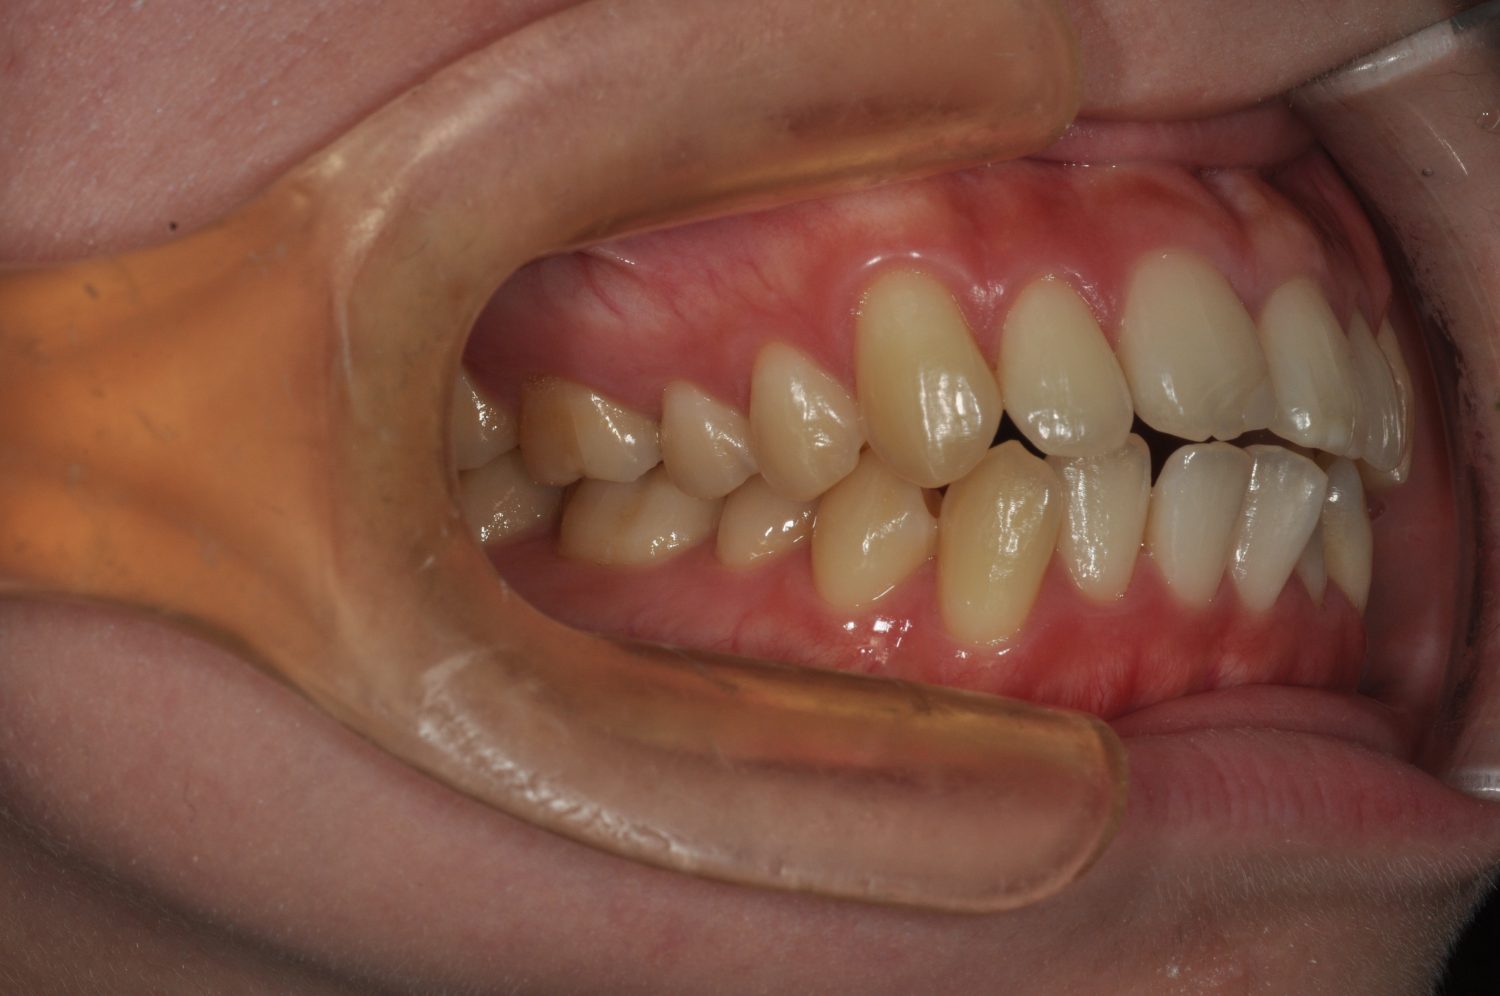

| 主訴 | 前歯の出っ歯を直したい |

| 治療内容 | 上下顎とも標準範囲であるが、上下顎前歯ともに唇側傾斜による、上下顎前突。上顎小臼歯を抜去し配列を行うこととした。 |

| 治療費 | Ⅱ期治療費:770,000円 (税込) 調整料 5,500円 (税込)×23回 保定時:22,000円 (税込) 計 918,500円 (税込) |

| 治療期間 | 2年1ヶ月 |

| 治療回数 | 25回 |

| 想定されたリスク | 矯正器具の装着に伴い、むし歯や歯周病のリスクがありました。また、歯根吸収や歯肉退縮のリスクもありました。 |

上下顎前歯の唇側傾斜による上下顎前突。オーバージェットが大きいため、上顎のみの抜歯で配列を行った。